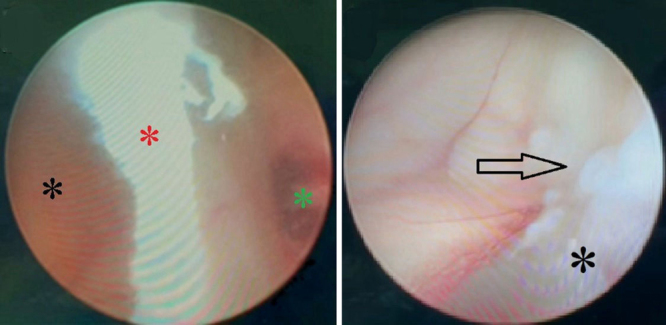

Observations: A 47-year-old female presented with a 3-month history of short-term memory disturbances, ultimately leading to loss of consciousness. Neuroimaging revealed symmetrical biventricular hydrocephalus accompanied by periventricular interstitial edema. A lumbar puncture indicated lymphocytic-dominant pleocytosis and reduced glucose levels. During the endoscopic approach, significant stenosis of the foramen of Monro was noticed and monroplasty and septostomy were performed. Pathological examination revealed granulomatous inflammation. At the 1-year follow-up, the patient demonstrated significant clinical and radiological improvement, with resolution of symptoms and hydrocephalus.

Lessons: Tuberculosis-induced bilateral idiopathic occlusion of the foramen of Monro is an extremely uncommon cause of hydrocephalus. Neuroendoscopy allows for visualization, biopsy, and direct treatment of the obstruction simultaneously. While conservative management may be adequate for asymptomatic cases, neuroendoscopic procedures such as septostomy or foraminoplasty provide a minimally invasive option for restoring CSF flow, avoiding unnecessary shunt insertion in symptomatic cases. https://thejns.org/doi/10.3171/CASE25349.

Abstract Image